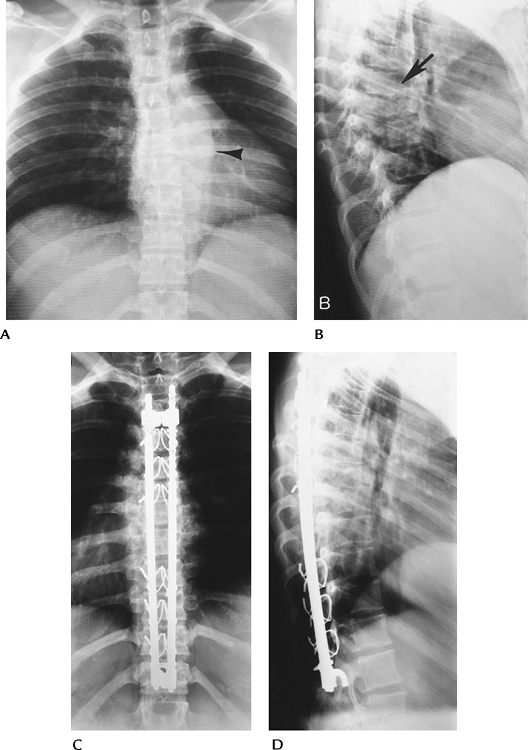

![]() |

FIGURE 3-44 Standing AP (A) and lateral (B) radiographs after reduction with rods and hooks.

P.87

|

FIGURE 3-45 Lateral radiograph with fractured Luque rods (arrow) after treatment with rods and sublaminar wires.